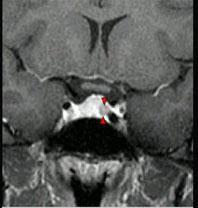

女,38岁,头痛、闭经,MRI检查如图,选择最可能的诊断()A.垂体囊肿B.垂体梗死C.转移瘤D.垂体微腺瘤E.垂体脓肿

问题 女,38岁,头痛、闭经,MRI检查如图,选择最可能的诊断()

选项 A.垂体囊肿 B.垂体梗死 C.转移瘤 D.垂体微腺瘤 E.垂体脓肿

答案 D